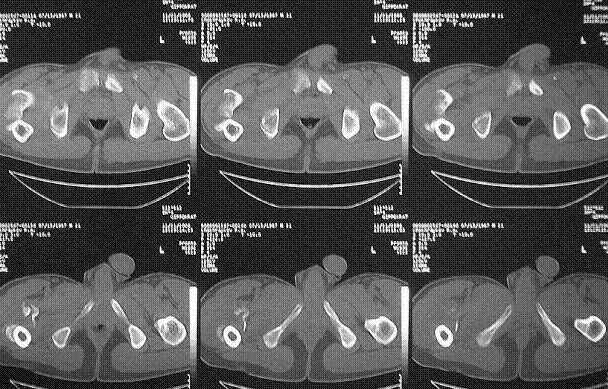

Уважаемые коллеги! Нужен совет.Больной Х., 21 год, ДЗ: ложный сустав вертельной области правого бедра.

Травма 8 мес. назад, ДТП, получил закрытый межвертельный перелом правого бедра. Лечился в городской больнице одного из городов-спутников г. Караганды скелетным вытяжением в течение 3 недель, затем кокситной гипсовой повязкой 2 мес. В настоящее время имеется укорочение конечности на 7 см, умеренная боль в вертельной области; ходит без костылей, полностью нагружая больную конечность, при нагрузке отмечается смещение дистального отломка проксимально примерно на 1,0 см.; объем движений в коленном суставе сохранен; при пальпации отломков боли нет, умеренная патологическая подвижность. Планируем внеочаговый остеосинтез спице-стержневым аппаратом, дистракция до восстановления длины бедра, вторым этапом остеосинтез стержнем Гамма. Есть надежда, что на дистракции пойдет сращение и у больного хватит терпения завершить лечение в аппарате.

Если судить по снимкам, то укорочение кажеться не критическим, но обьективно и на 3D - укорочение на 6-7 см.